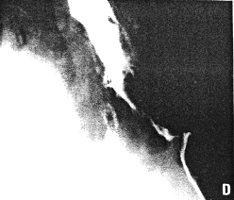

Case 35.1S.S., 67 year old male, presented with increasing dysphagia. Radiographic examination showed a constant, irregular filling defect of the lower 5.0 to 6.0 cm of the oesophagus, typical of carcinoma; it extended as far as the gastro-oesophageal junction, i.e. through the oesophageal hiatus in the diaphragm (Fig. 35.1D). The pyloric sphincteric cylinder showed a constant contraction, appearing to be "fixed" midway between maximum contraction and maximum dilatation, with absent cyclical activity (Fig. 35.1A-C). Most of the time the pyloric aperture contained barium, i.e. it was patent; at times it contained a single mucosal fold. At oesophagoscopy only the upper border of the carcinoma could be visualized; biopsy was unsuccessful. Repeat radiography a month later showed extension of the oesophageal lesion with only a trickle of barium entering the stomach.

| Fig. 35.1. A-DCase S.S. A-C Constant contraction pyloric sphincteric cylinder with absent cyclical activity. D Irregular filling defect lower oesophagus extending through diaphragmatic hiatus, indicating carcinoma. | |